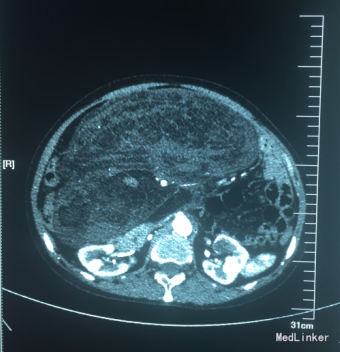

腹部触诊可触及巨大包块,大小约21*17cm,质地韧,活动度差。全腹部+盆腔CT示:,腹腔内巨大软组织肿块,呈混杂密度,内含脂肪及增强血管影,腹部肠管,右肾及周围组织明显受压移位,考虑脂肪肉瘤可能;右侧附件区畸胎瘤;肝脏及双肾可见小圆形低密度灶,边缘光滑,考虑肝多发囊肿,右肾囊肿;盆腔少量积液。

术中将腹壁切开,探查可见肿瘤大小约33*30*15cm,质地韧,不均匀,肿块基地部较大与空肠起始部相连,与周围肠管轻度粘连,空肠起始部系膜表面可见脂肪样包块突起,直径约3-5cm,基底部较宽,与肠系膜相连;余肠系膜再见包块,右下腹可见一直径约10cm略呈球形包块,质地韧包膜完整,仅仅可见一蒂与肠系膜相连。术后病理诊断为:“腹腔”多发性高分化脂肪肉瘤(脂肪瘤样型),部分区混合粘液性脂肪肉瘤,(约占10%)伴局部脂肪坏死及钙化。